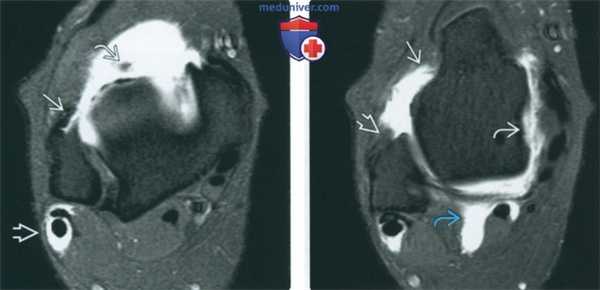

(Слева) МР-артрография в режиме Т1ВИ, коронарный срез, пациент 25 лет: визуализируется обширное повреждение суставного хряща подтаранного сустава вследствие перелома пяточной кости.

(Справа) МР-артрография в режиме Т1 ВИ, сагиттальный срез: спереди видны участки неизмененного хряща, а сзади - выраженное его истончение. В голеностопном суставе отмечаются признаки остеоартроза. У этого пациента подтаранный сустав сообщается с полостью голеностопного сустава. Лечение заключалось в артродезе обоих суставов.